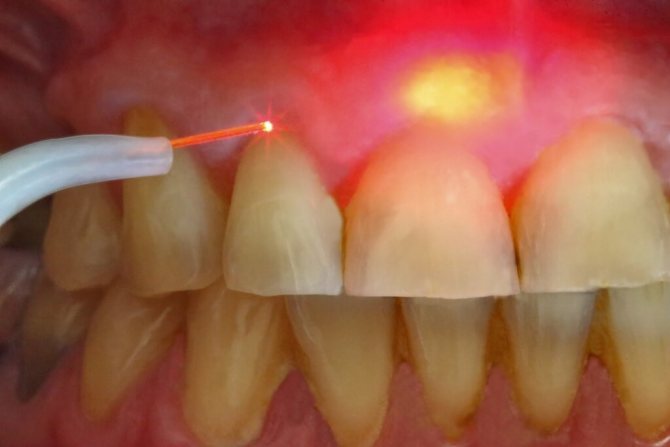

Стоматологическая помощь

При любой форме стоматита, лечение начинают с профессиональной чистки ротовой полости. Слизистую обрабатывают антисептиками. Больному рекомендуют регулярно полоскать рот отварами трав, обладающих противомикробным действием. Если есть кариес или другие болезни зубов, рекомендуется их вылечить. Отсутствие воспалительных процессов снижает риск повторного появления язв.